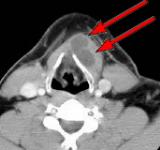

HELICAL CT FINDINGS: The CT scan was performed on AIC’s Multi-slice, Multi-detector Helical CT Scanner with 2.7 mm axial sections at 2.5 mm intervals before and during infusion of low-osmolar, non-ionic contrast using a power injector. It shows a lobulated cystic mass (arrows) in the neck at and below the hyoid bone in the midline and to the left of it, with portions of it behind the hyoid bone and portions embedded in the left strap muscle.